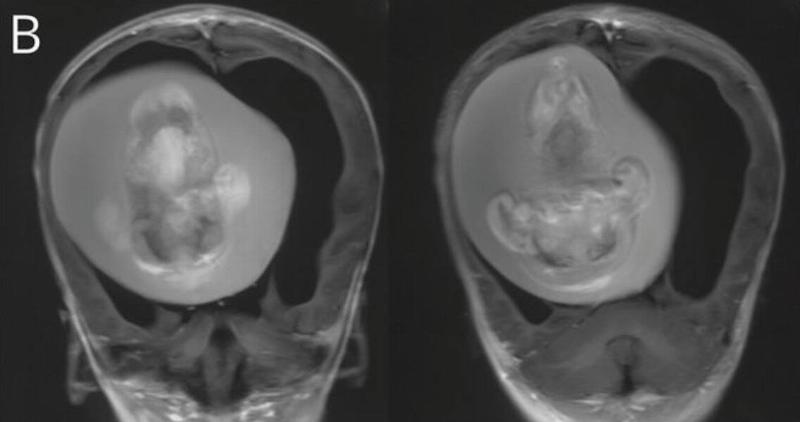

Once the CT scans revealed the existence of her twin that was pressing against her brain, doctors knew they had to remove it immediately. By the time they were able to extract it, it had been growing inside the girl's skull for months, long enough for it to develop bones, organs, and limbs.

Dr. Zongze Li, a neurologist at Huashan Hospital who treated the girl, said, "The intracranial fetus-in-fetu is proposed to arise from unseparated blastocysts. The conjoined parts develop into the forebrain of the host fetus and envelop the other embryo during neural plate folding."

Though this type of case is exceedingly rare, it's not the first time a parasitic twin has been discovered inside a child's skull. In 2017, doctors in Thailand found not just one, but three siblings inside the skull of an unborn girl.

They said that each sibling has "multiple well-developed organs" which included a nervous, digestive, and respiratory system. They were all connected to the host sibling by a single artery and vein, which doctors said had once been the umbilical cord.